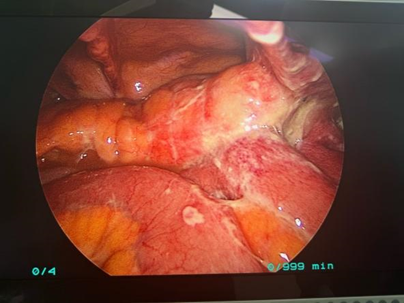

术中发现:乙状结肠多发憩室,长约 20 cm,其中直乙交界处可见一憩室穿孔,穿孔大小约 0.5*0.5 cm,穿孔处可见少量粪水流出。其余憩室壁薄,炎症明显。

结肠及部分小肠壁大量黄色脓苔附着,肠壁及系膜水肿增厚明显。盆腔、左侧结肠旁沟及部分小肠系膜间隙有粪水样液体残留。肝、胆、胃及其余肠管未见明显异常。